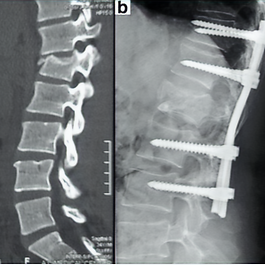

Spine Trauma Surgery

X-Ray the L1 fracture, which is fixed by long-segment pedicle screw fixation